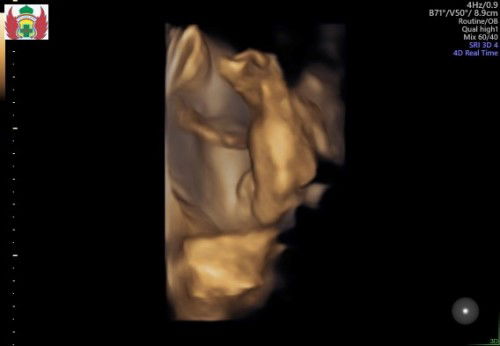

Ada yg sama ga bunda. Tadi saya memastikan karna kalo hpl bidan lewat mau 10 hari. Akhirnya saya ke dr kandungan ternyata UK baru 38week dan hpl 20 April. Semuanya normal mulai ketuban plasenta . Kata bidan pas d periksa ini bayinya udah gede udah mau 4kg disitu saya khawatir stres mikirin mana udh lewat hpl mana bayi gede. Ternyata tadi USG bayi nya bbj 2.8kg#bantusharing